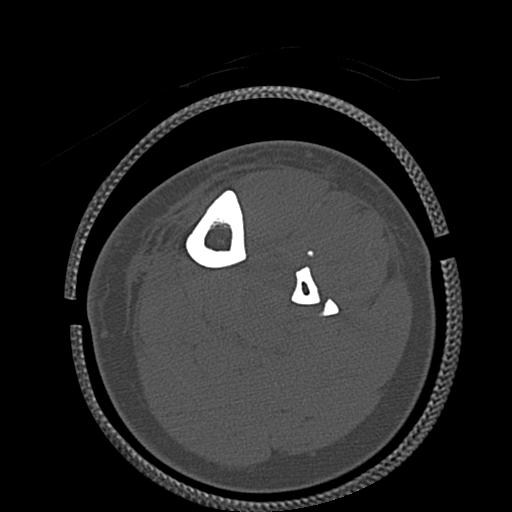

102803 1/12(キウスなし) 1/27 左下腿 4R 30歳女性 左脛骨軸内釘